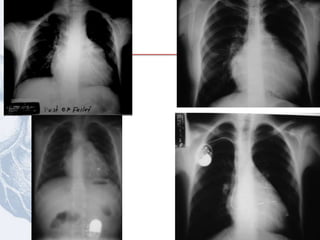

Radiografía de tórax

Cardiomegalia leve

Arco de la pulmonar excavado

Levantamiento de la punta del corazón

Oligohemia pulmonar

Arco aortico derecho (25%)